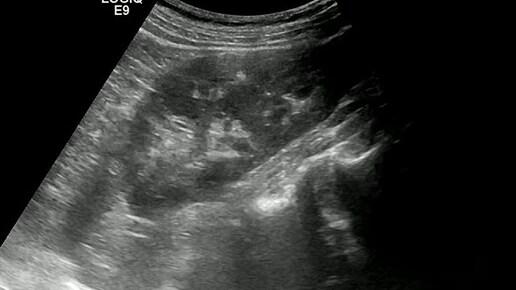

Ультразвуковые находки от врача УЗД Зорина Я.П.